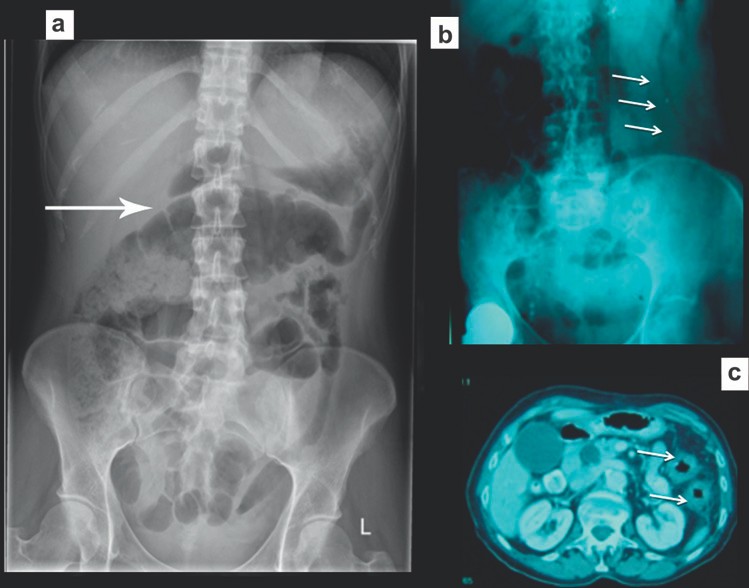

Các dấu hiệu trên phim thường quy là các quai ruột non bị giãn, đường kính trên 30 mm ở đoạn gần và trên 25 mm ở đoạn xa. Các mức khí dịch có chân rộng hơn 25mm là bất thường, các mức khí-dịch của một quai ruột ở các độ cao khác nhau (hình bậc thang) và các bóng khí bị kẹt giữa các quai ruột giãn (dấu hiệu hình tràng hạt) cũng là dấu của hiệu tắc ruột. Ít phổ biến, nếu các quai ruột bị giãn chứa đầy dịch thì phim X quang bụng cho thấy các quai ruột trong ổ bụng rất ít khí làm tăng nghi ngờ tắc ruột ở bệnh nhân có triệu chứng lâm sàng. Các dấu hiệu X quang có thể xuất hiện trước các triệu chứng lâm sàng từ 6 đến 12 giờ. Hình 1 cho thấy một vài dấu hiệu X quang của tắc ruột non.

Hình 1. Tắc ruột non. (a) Nhiều quai ruột non giãn, chứa đầy khí. Lưu ý nhiều nếp vòng theo chu vi ruột. (b) Rất ít khí do ruột non bị tắc chứa đầy dịch. (c) Phim X quang bụng chụp đứng cho thấy nhiều mức khí dịch-hình “bậc thang”.